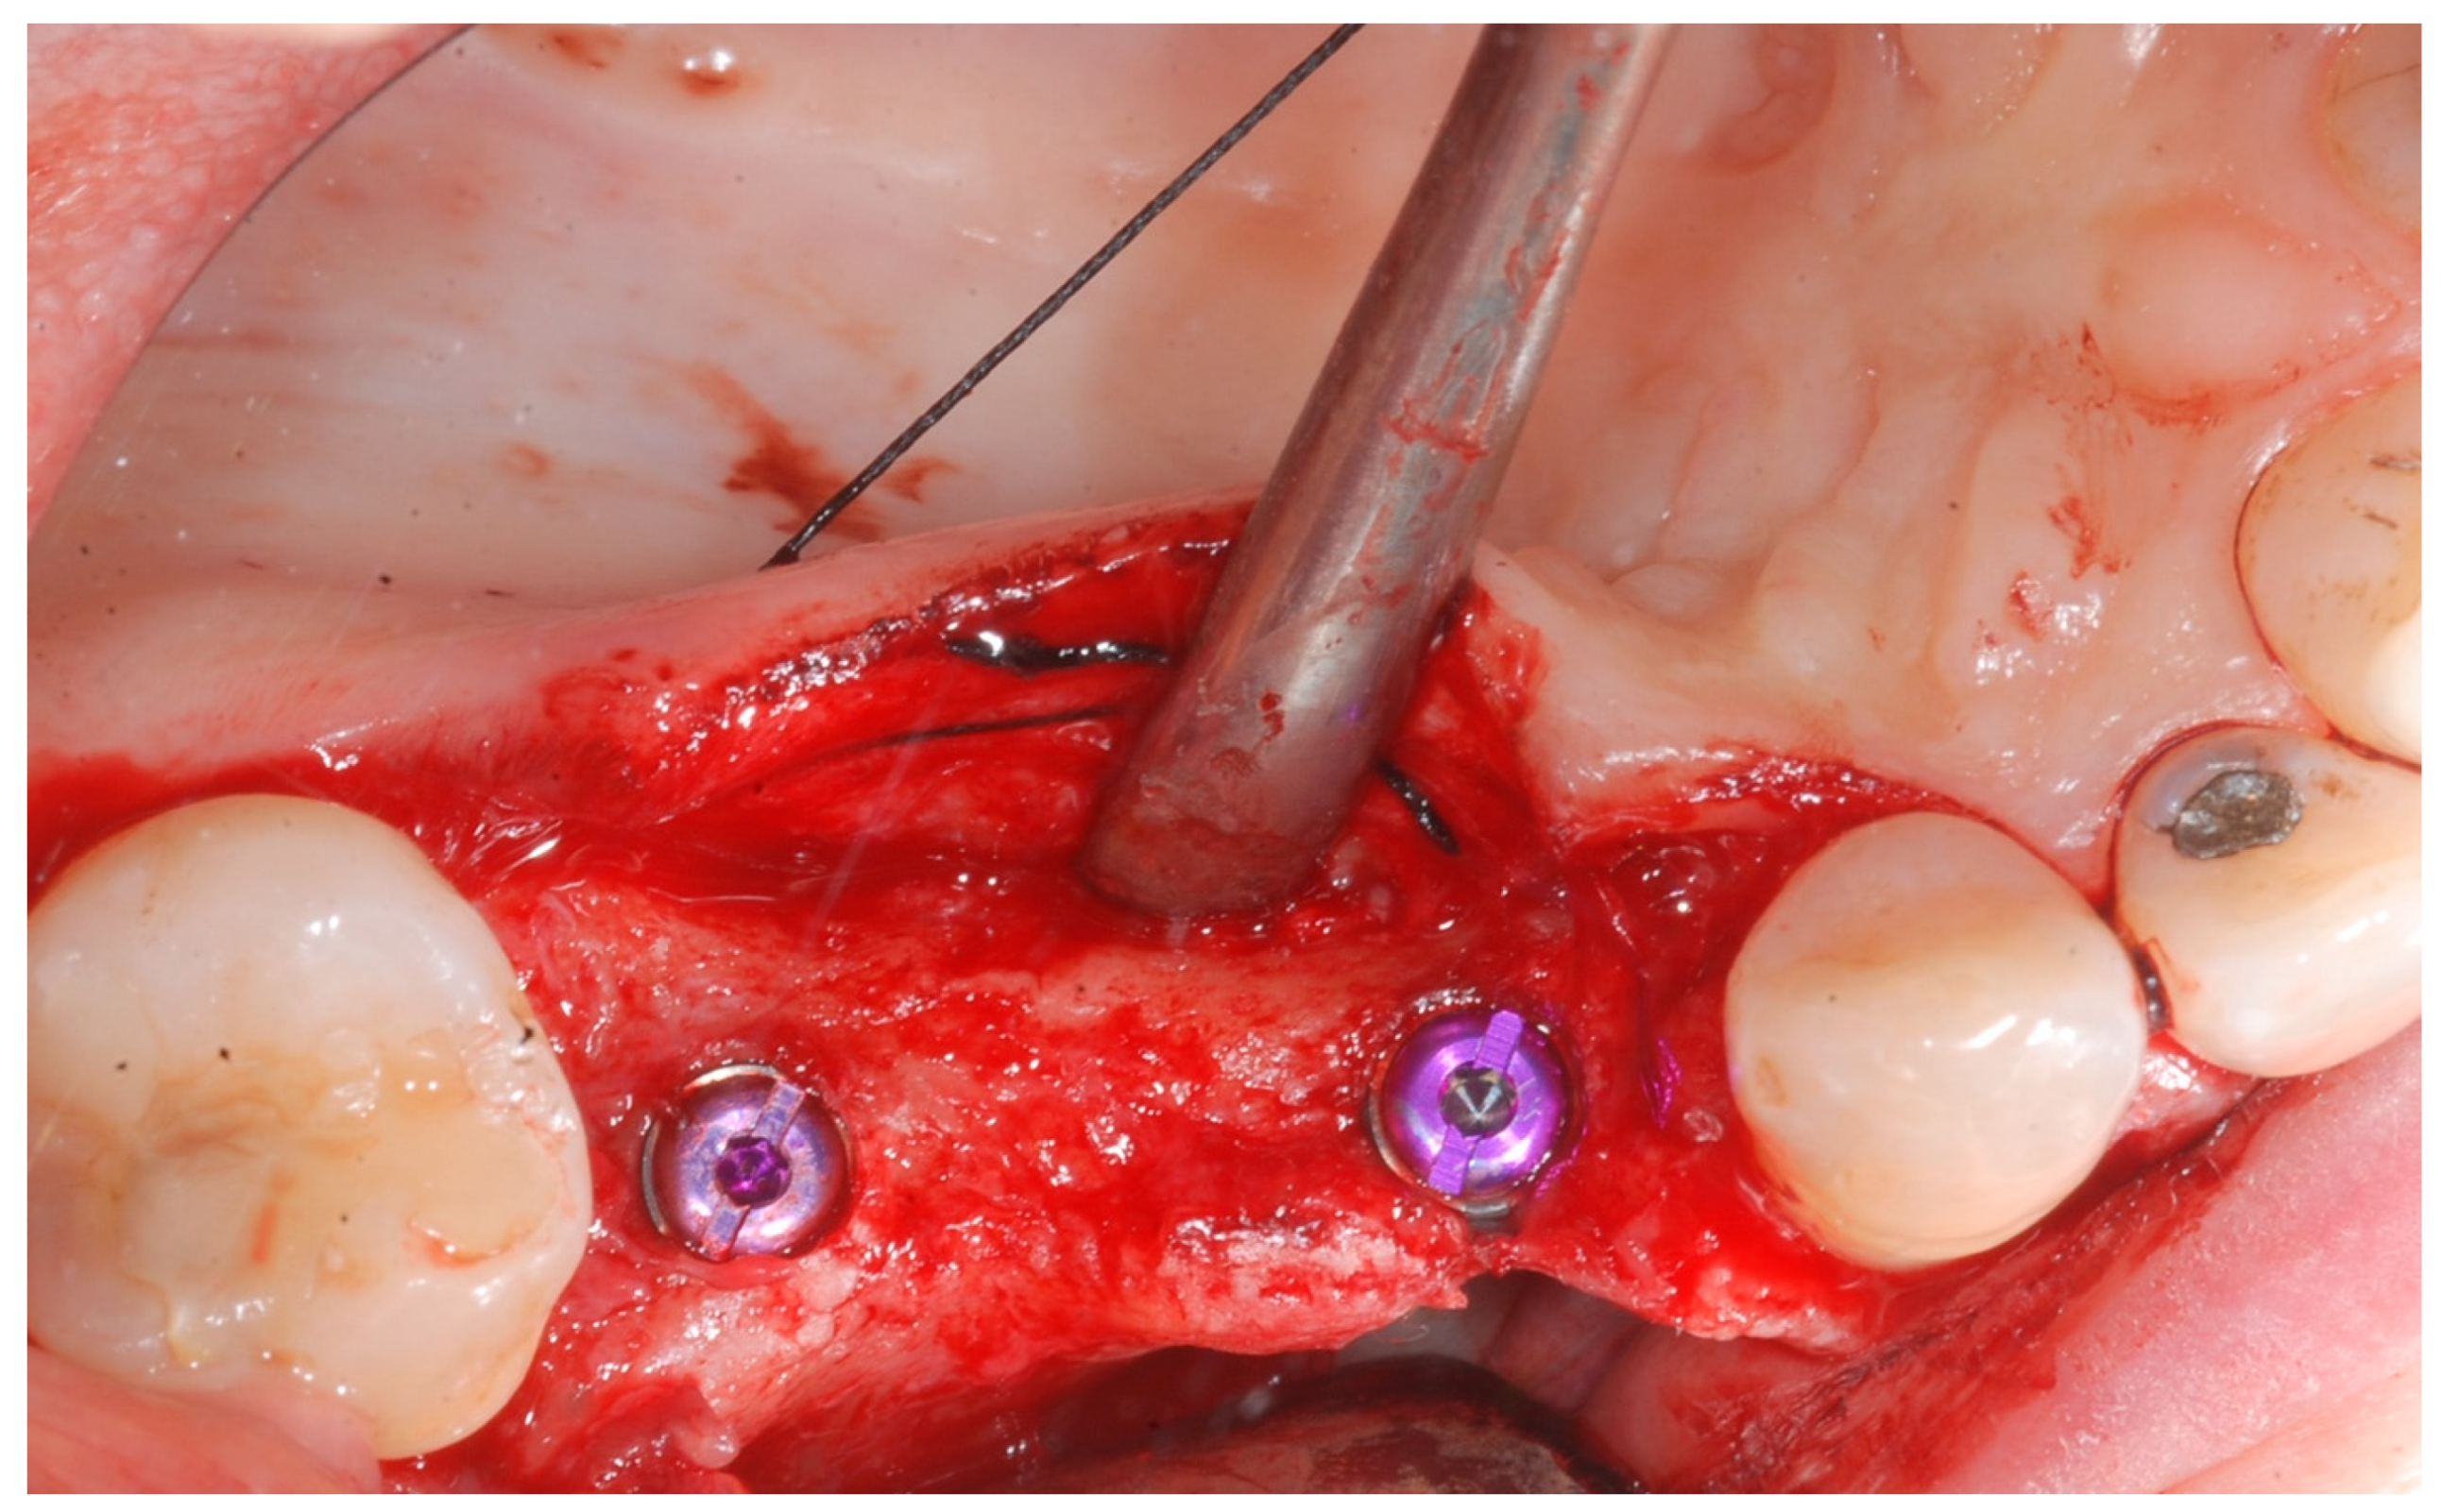

At this point, implants were placed according to the manufacturer’s instructions in a prosthetically ideal position with the aid of the surgical stent (Figure 3 and Figure 4).

Figure 4.

Implant positioning and cover screws in place.